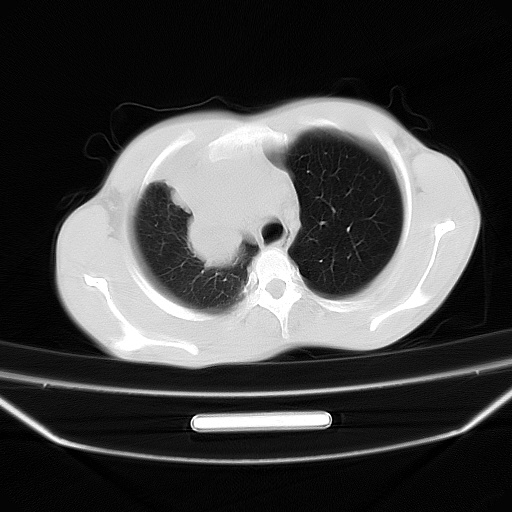

以下是引用zjzjr在2008-7-20 12:57:00的发言:[br]考虑为生殖源性肿瘤(内胚窦瘤),侵袭性胸腺瘤可能性大;右侧少量胸腔积液。

以下是引用xinliheng001在2008-7-20 21:17:00的发言:[br]右纵隔巨大分叶状软组织均质密度肿块,右上肺叶受压明显,纵隔右移、胸膜受累有少量积液和结节样增厚。应增强扫描一定会有更具诊断价值的信息。

以下是引用xinliheng001在2008-7-20 21:17:00的发言:[br]右纵隔巨大分叶状软组织均质密度肿块,右上肺叶受压明显,纵隔右移、胸膜受累有少量积液和结节样增厚。应增强扫描一定会有更具诊断价值的信息。